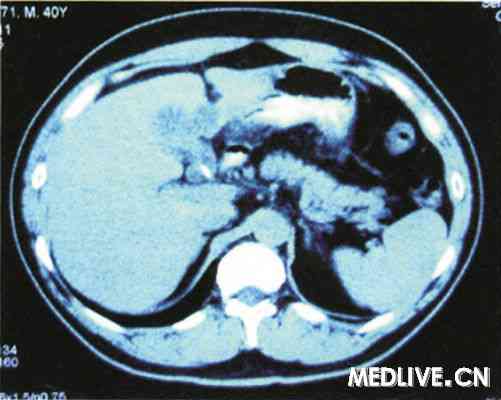

上腹部CT平扫(图1)示:肝脏表面光整,肝脏实质密度减低,胆囊颈部可见点状高密度区,胆囊实质内密度不均匀:进一步行增强CT(图2)示:胆囊壁明显强化,胆囊窝前内侧可见软组织样密度影; 影像诊断:胆囊结石,脂肪肝,胆囊窝积液。

(图1 入院上腹部CT平扫 图2上腹部CT增强)